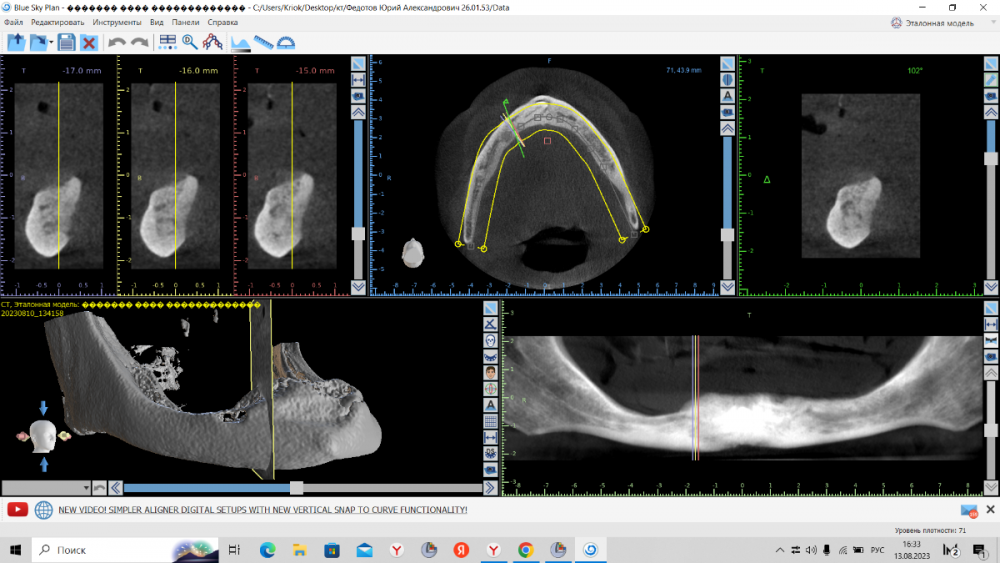

kriokov Опубликовано 10 августа, 2023 Поделиться Опубликовано 10 августа, 2023 ретенция клыка справа. кость 1 тип. Выход нерва почти по вершине. Сьемник не держится. М- 70 лет. Здоров. Нужен совет по установке имплантата справа под локатор, без удаления клыка. Слева штатно. Ссылка на комментарий

kriokov Опубликовано 12 августа, 2023 Автор Поделиться Опубликовано 12 августа, 2023 Вариантов не много. Поговорю с пациентом. 1. Склоняюсь к тому, что предложу установить имплантат в позиции, где он апикально в корне ретенированного. 2. менее предпочтительно из за травматизма- удаление клыка, имплантация 3. установка имплантата по косой сразу за выходом нерва, есть возможность миновать корень , направление имплантата так себе. Спасибо всем за обсуждение. 6 часов назад, Irouil сказал: Фиброзный пульпит будет и все, что такого? удаляли 36, пилили медиальный корень, hit root 35 в нижней трети (видимо потеряли визуализацию в ране + корень с изгибом в сторону 36), внешняя резорбция корня 35 через пару лет, пульпа сдохла, эндодонтия , теперь наблюдаем. Ссылка на комментарий

annda Опубликовано 13 августа, 2023 Поделиться Опубликовано 13 августа, 2023 (изменено) Предположу, что это должны быть как раз первые 4- 6 мм имплантата , корональная его часть( как при синус лифтинге том же) . в данном кейсе ( на втором соезе, что показан) совсем же другая ситуация. В этом ракурсе можно срез посмотреть не через коронку клыка, а через апикальную треть корня, над которым как раз и лежит массив своей губчатой кости.Посмотреть, сколько его там. А самый первый срез чем не устраивает ?Там область за местом выхода СНП или я не понимаю чего-то? Изменено 13 августа, 2023 пользователем annda Ссылка на комментарий

TIGER Опубликовано 13 августа, 2023 Поделиться Опубликовано 13 августа, 2023 2 импланта под 30 гр м.ю,балочка между ними,и никакого гемора с клыком и локаторами Ссылка на комментарий

kriokov Опубликовано 13 августа, 2023 Автор Поделиться Опубликовано 13 августа, 2023 10 часов назад, annda сказал: А самый первый срез чем не устраивает ?Там область за местом выхода СНП или я не понимаю чего-то? Думаю првильно понимаете, это более менее позиция, 6 часов назад, TIGER сказал: 2 импланта под 30 гр м.ю,балочка между ними,и никакого гемора с клыком и локаторами как вариант, да + Ссылка на комментарий